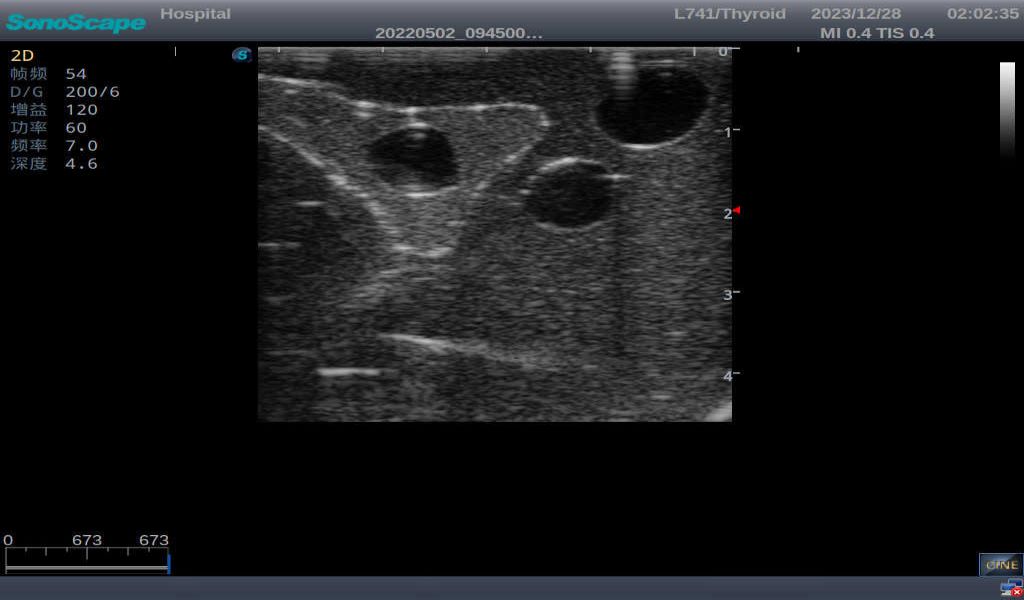

3)       It comes with four (4) thyroid modules and can show five (5) ultrasonic images: normal thyroid, thyroid adenoma, thyroid cancer, nodular goiter, thyroid cyst

Normal thyroid with homogeneous parenchymal echo and well-defined capsule

Thyroid adenoma with well-defined border and smooth uniform halo

Thyroid cancer with irregular mass, unclear border, uneven internal echo or calcification strong echoes

Nodular goiter with irregular border and varying sizes of low echo, isoechoic, or high echo nodules

Thyroid cyst, which fluid area, dark and echo-free area can be seen